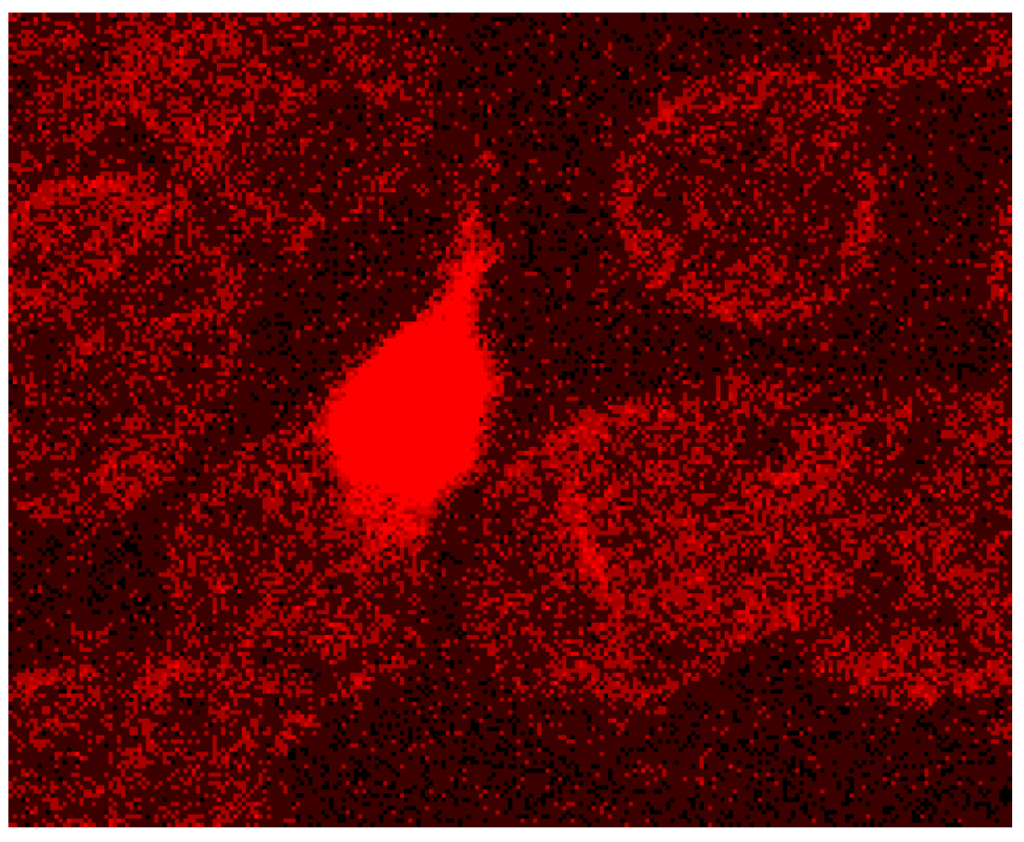

Different from strong changes in the distribution of band 4.9, there were only weak changes in the distribution of band 3 after erythrocyte suspension in an Iodixanol/plasma mixture (see Figure 17A). Changes in band 3 localization were remarkable after erythrocyte contact with Iopromide. A condensation of knoblike structures at the cell rim was observed coinciding with a strong decrease in stain intensity in the cell center and a slight increase of band 3 and spectrin co-localization (yellow shift) in the knob-like structures (see Figure 17B).

Figure 17. Merger of red (band 3) and green (spectrin) channels of the confocal microscope after examination of double stained erythrocytes suspended in RCM/plasma mixtures (reprinted from reference [21]). (A) Erythrocyte suspended in Iodixanol/plasma mixture (30% v/v); (B) Erythrocyte suspended in Iopromide/plasma mixture (30% v/v). (Primary magnification: 1:63; zoom factor 5).

Band 3 is described to constitute a center organized into complexes for gas transport [41,42,43,44], anion exchanger, for glycolysis [43,45,46], for the control of cell volume [47] and of erythrocyte life span (senescence) [48], where most probably further complexes exist to cope with mechanical deformation [49], and haemostatic stimuli [50,51]. The drastic reorganization of the band 3—spectrin network affected by suspension of erythrocytes in an Iopromide/plasma mixture coincided with a strong alteration of the spectrin network and a clustering of band 3 in very few highly condensed centers at the rim of the cells (see Figure 18). This is most probably accompanied by a strong increase in membrane stiffness (contributing to microcirculatory disorders shown in patients with coronary artery disease after Iopromide application during coronary angiography [10]). Together with translocation of band 3 particles out of erythrocytes, a strong decrease of centers for gas transport can be expected, contributing to hypo-oxygenation of the tissue, as was shown after Iopromide application in the myocardium of pigs [12] but not after Iodixanol application [52]. The clustering of band 3 is assumed to lead to a shortening of the lifespan and removal of erythrocytes by offering senescence signals. The remarkable loss of band 3, revealed by a sequestration of band 3 out of the tips of the spicules, is thought to give clear evidence that the echinocyte formation provoked by RCM is associated with an exocytotic process—a mechanism which was not described up to now.